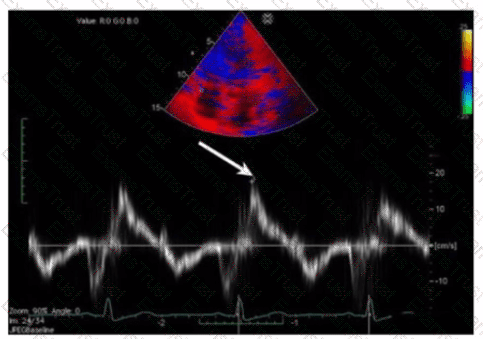

What is indicated by the arrow on this video clip?